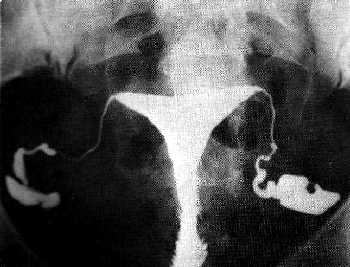

Hamile kalmakta güçlük çeken kadınlarda endometriozis hastalığı görülme olasılığı artmaktadır. Bu kadınların bir kısmında, özellikle de ileri evre endometriosis hastalığı olanlarda, endometriozisin neden olduğu tahribat Fallop tüplerinde (rahim kanalları) tıkanıklığa yol açmaktadır.

Hamile kalmakta güçlük çeken kadınlarda endometriozis hastalığı görülme olasılığı artmaktadır. Bu kadınların bir kısmında, özellikle de ileri evre endometriosis hastalığı olanlarda, endometriozisin neden olduğu tahribat Fallop tüplerinde (rahim kanalları) tıkanıklığa yol açmaktadır.